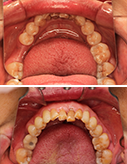

上下牙齿不齐隐形矫正案例